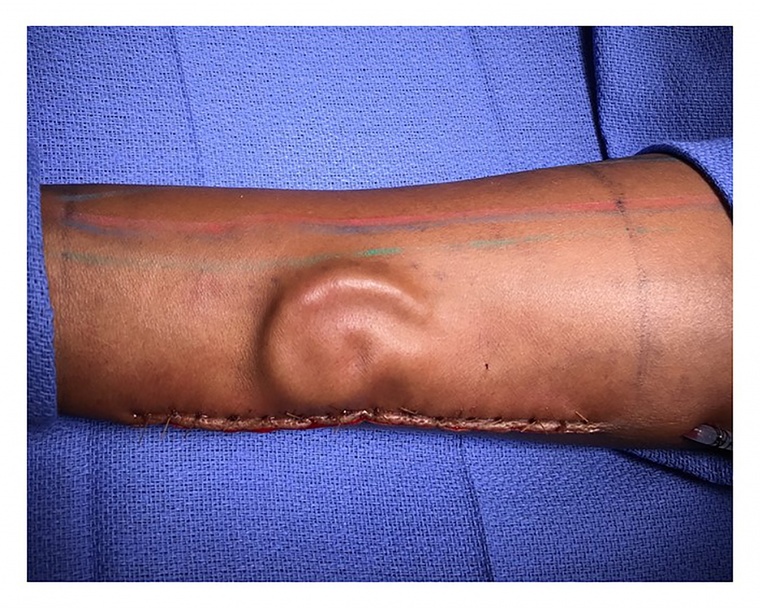

Americana tem orelha implantada no braço para melhorar recuperação de órgão

A soldado norte-americana Shamika Burrage, 21, foi submetida a método cirúrgico ainda pouco usado no mundo. Dois anos após perder a orelha em acidente de trânsito, ela teve teve o órgão implantado no braço para ser recuperado. O procedimento foi realizado pelo departamento médico da Marinha dos Estados Unidos.

Conforme a rede CNN, a orelha foi reconstituída com cartilagem da costela da soldado. Depois de atingir o formato ideal, a orelha foi retirada e colocada na cabeça de Shamika.

Segundo a equipe médica à frente da cirurgia, o período em que o órgão ficou no antebraço da americana, sob a pele, serviu para que reduzissem a probabilidade de cicatrizes, além de incentivar a formação de vasos sanguíneos, nervos e veias.